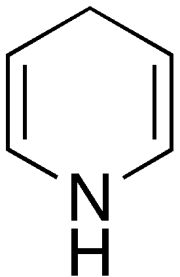

| 2021年7月26日 (一) 18:22 | Dihydropyridine.png (文件) |  |

3 KB | 77921020 | Uploaded with SimpleBatchUpload | 1 |